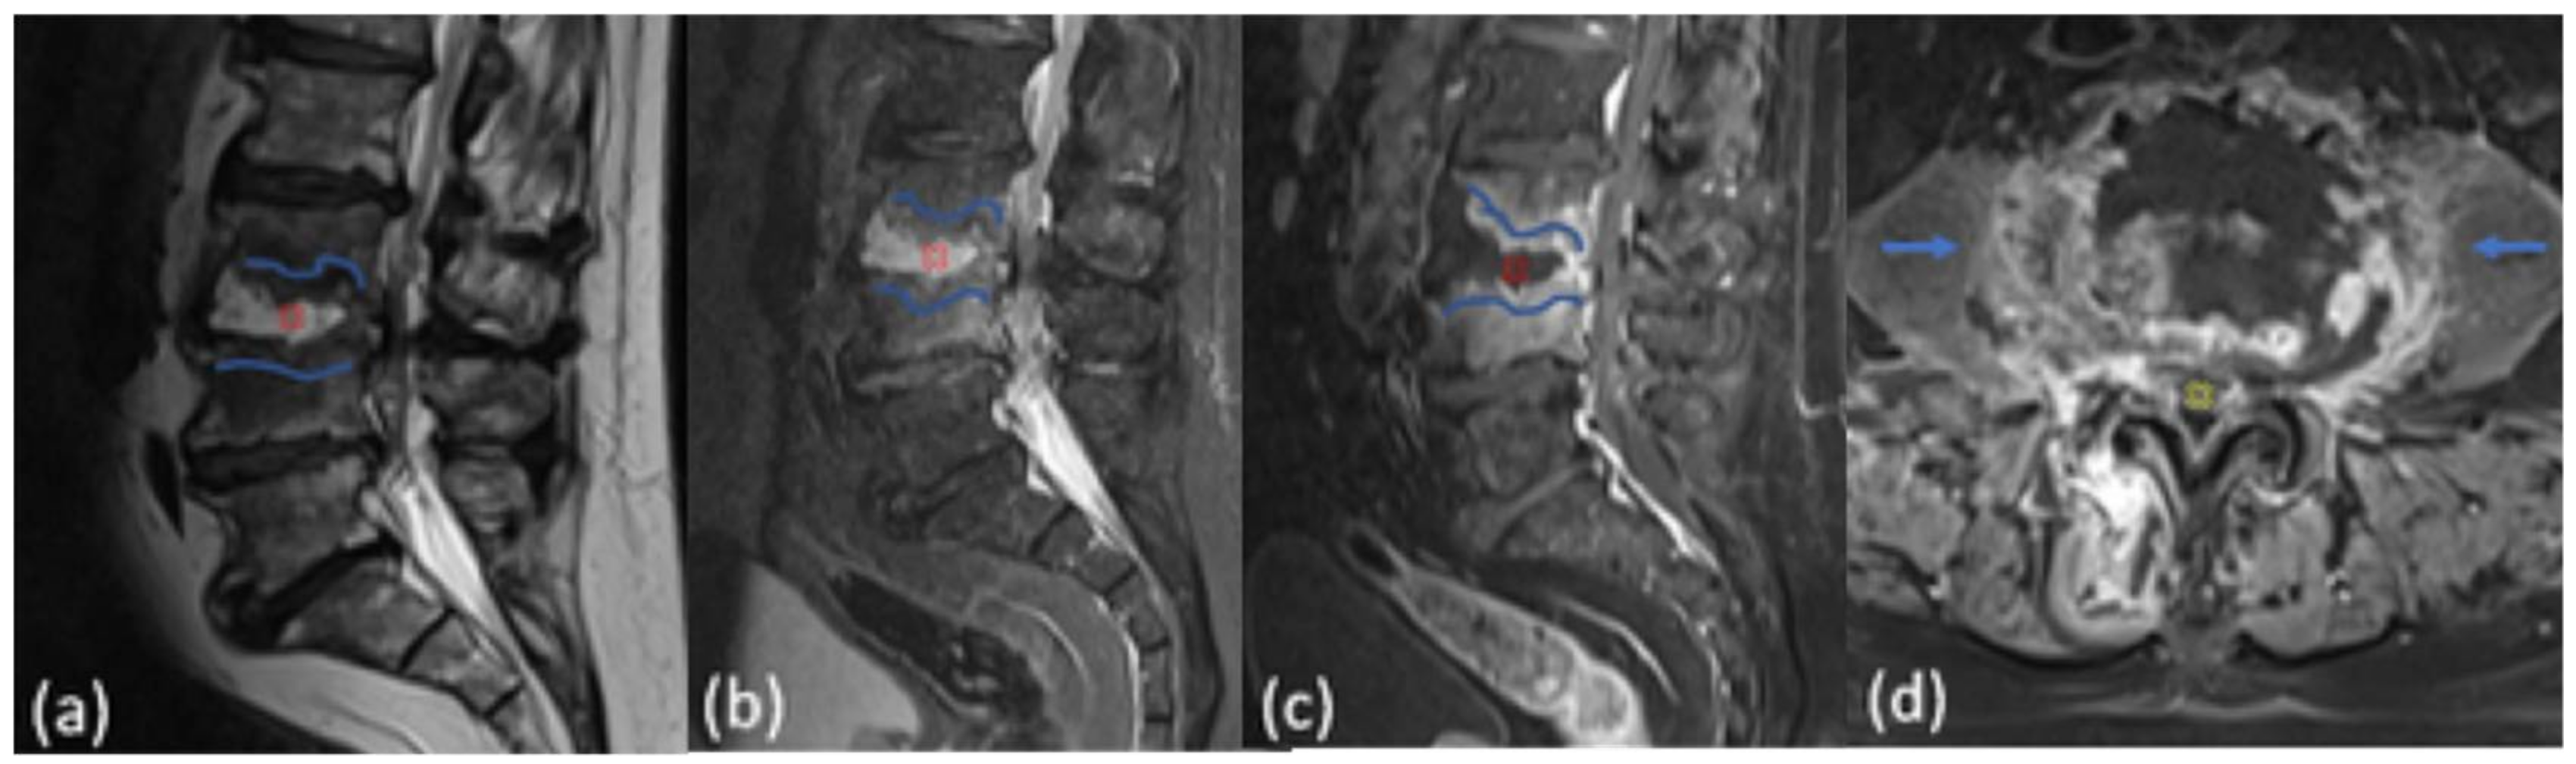

3. Results